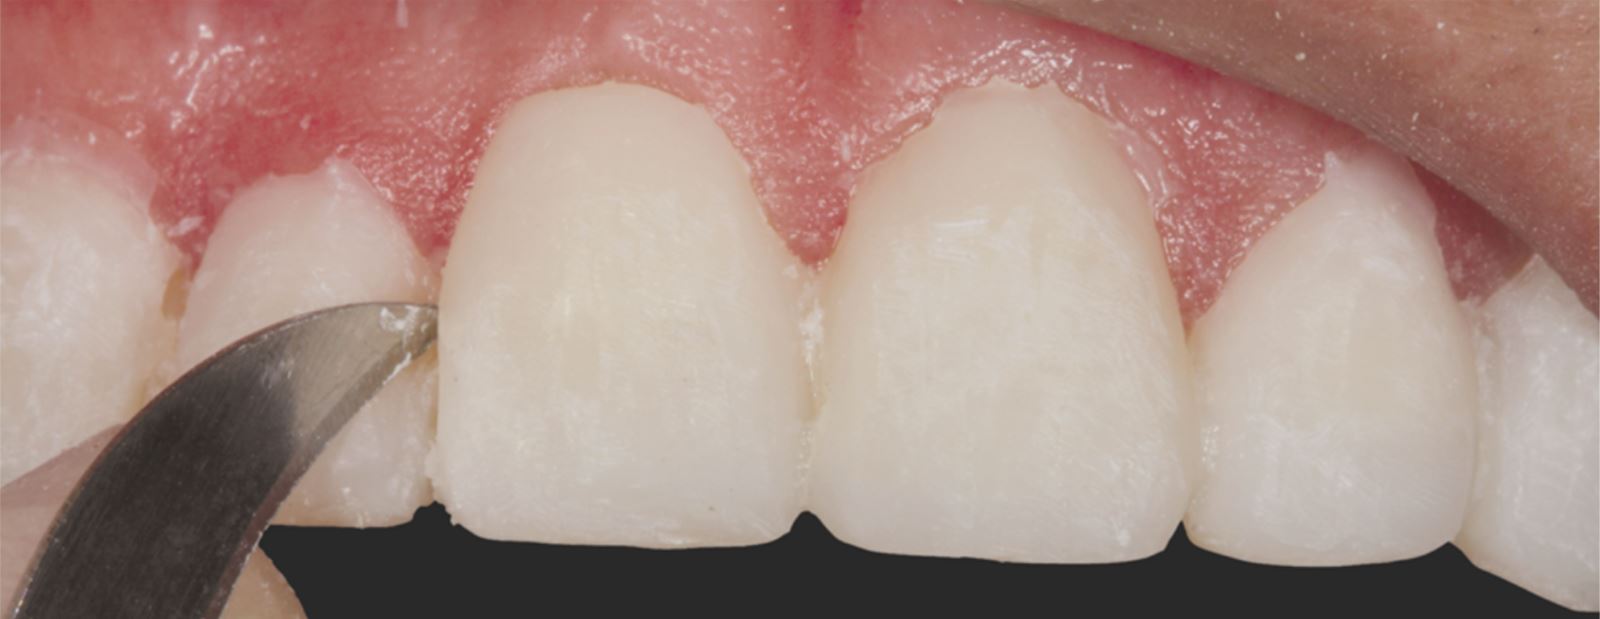

Príprava sulku:

Do gingiválneho sulku boli vložené pletené retrakčné vlákna Ultrapak™ veľkosti #0 na prípravu na leptanie.

Leptanie nepreparovanej skloviny:

Nepreparovaná sklovina bola leptaná 35% kyselinou fosforečnou Ultra-Etch po dobu 30 sekúnd.